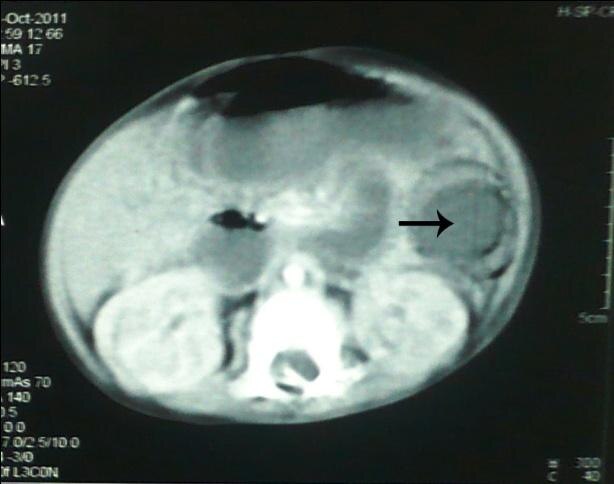

An CT scan of a belly, with arrow pointing at dark circle.

The arrow indicates a bowel obstruction in a six-month-old Pakistani child who died in 2012 after ingesting a gel ball.

A six-month-old boy in Pakistan swallowed a brightly coloured "gel ball" in 2012, which caused a bowel obstruction.

He then suffered a "burst abdomen" after surgical removal, developed septicemia and died two days after a second operation.